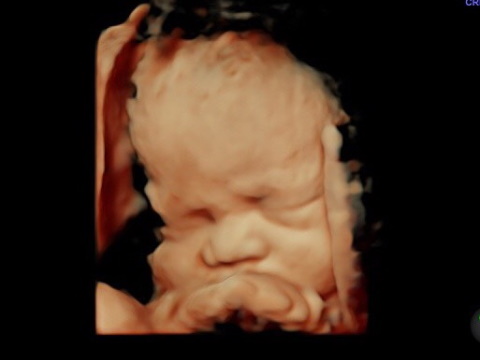

Se realiza entre la semana 18 a 24 de la gestación. Es un estudio que nos ayuda a determinar si tu bebe tiene alguna malformación en su anatomía. El ultrasonido estructural es un estudio realizado por ginecólogos con subespecialidad en Medicina Materno Fetal. Revisamos estructuras internas del cerebro, corazón , riñones , pulmones, manos y pies para ver si no tiene alteraciones en su anatomía. Se realiza además medición de tus arterias uterinas para estimar riesgo de preeclampsia y al final de tu estudio se realiza 3D , 4D. 5D para que conozcas la carita de tu bebe. Tiene una duración de 1 hora y un costo de $1800

El ultrasonido estructural o sonograma genético complementario, es un estudio muy importante que permite detectar o descartar una alta cantidad de defectos en el desarrollo físico del feto.